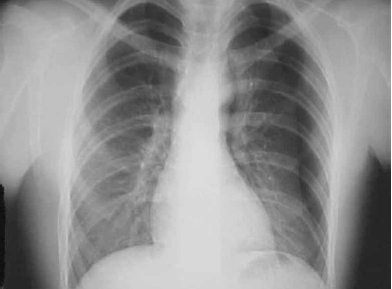

Homem de 38 anos deu entrada no Pronto-Socorro trazido por amigos, com relato de ferimento por arma branca em região do tronco à esquerda, após briga em um bar. Não houve atendimento pré-hospitalar. Chegou após 15 minutos do episódio e apresentava-se alcoolizado, agitado, reagindo a dor, com dificuldade para respirar e inspirações profundas e pausadas. Exame físico: ferimento penetrante por arma branca, de 6 cm de extensão em hemitórax esquerdo, no 6º EIC, com linha axilar média com presença de traumatopneia. Inspirações profundas e com pausas e uso de musculatura acessória. Presença de enfisema subcutâneo, diminuição da expansibilidade com hipertimpanismo à percussão e ausência de MV em HTE. FR = 24 mrpm . Saturação O2: 75%. PA: 115/74 mmHg. FC: 122 bpm. RX tórax demonstrado.